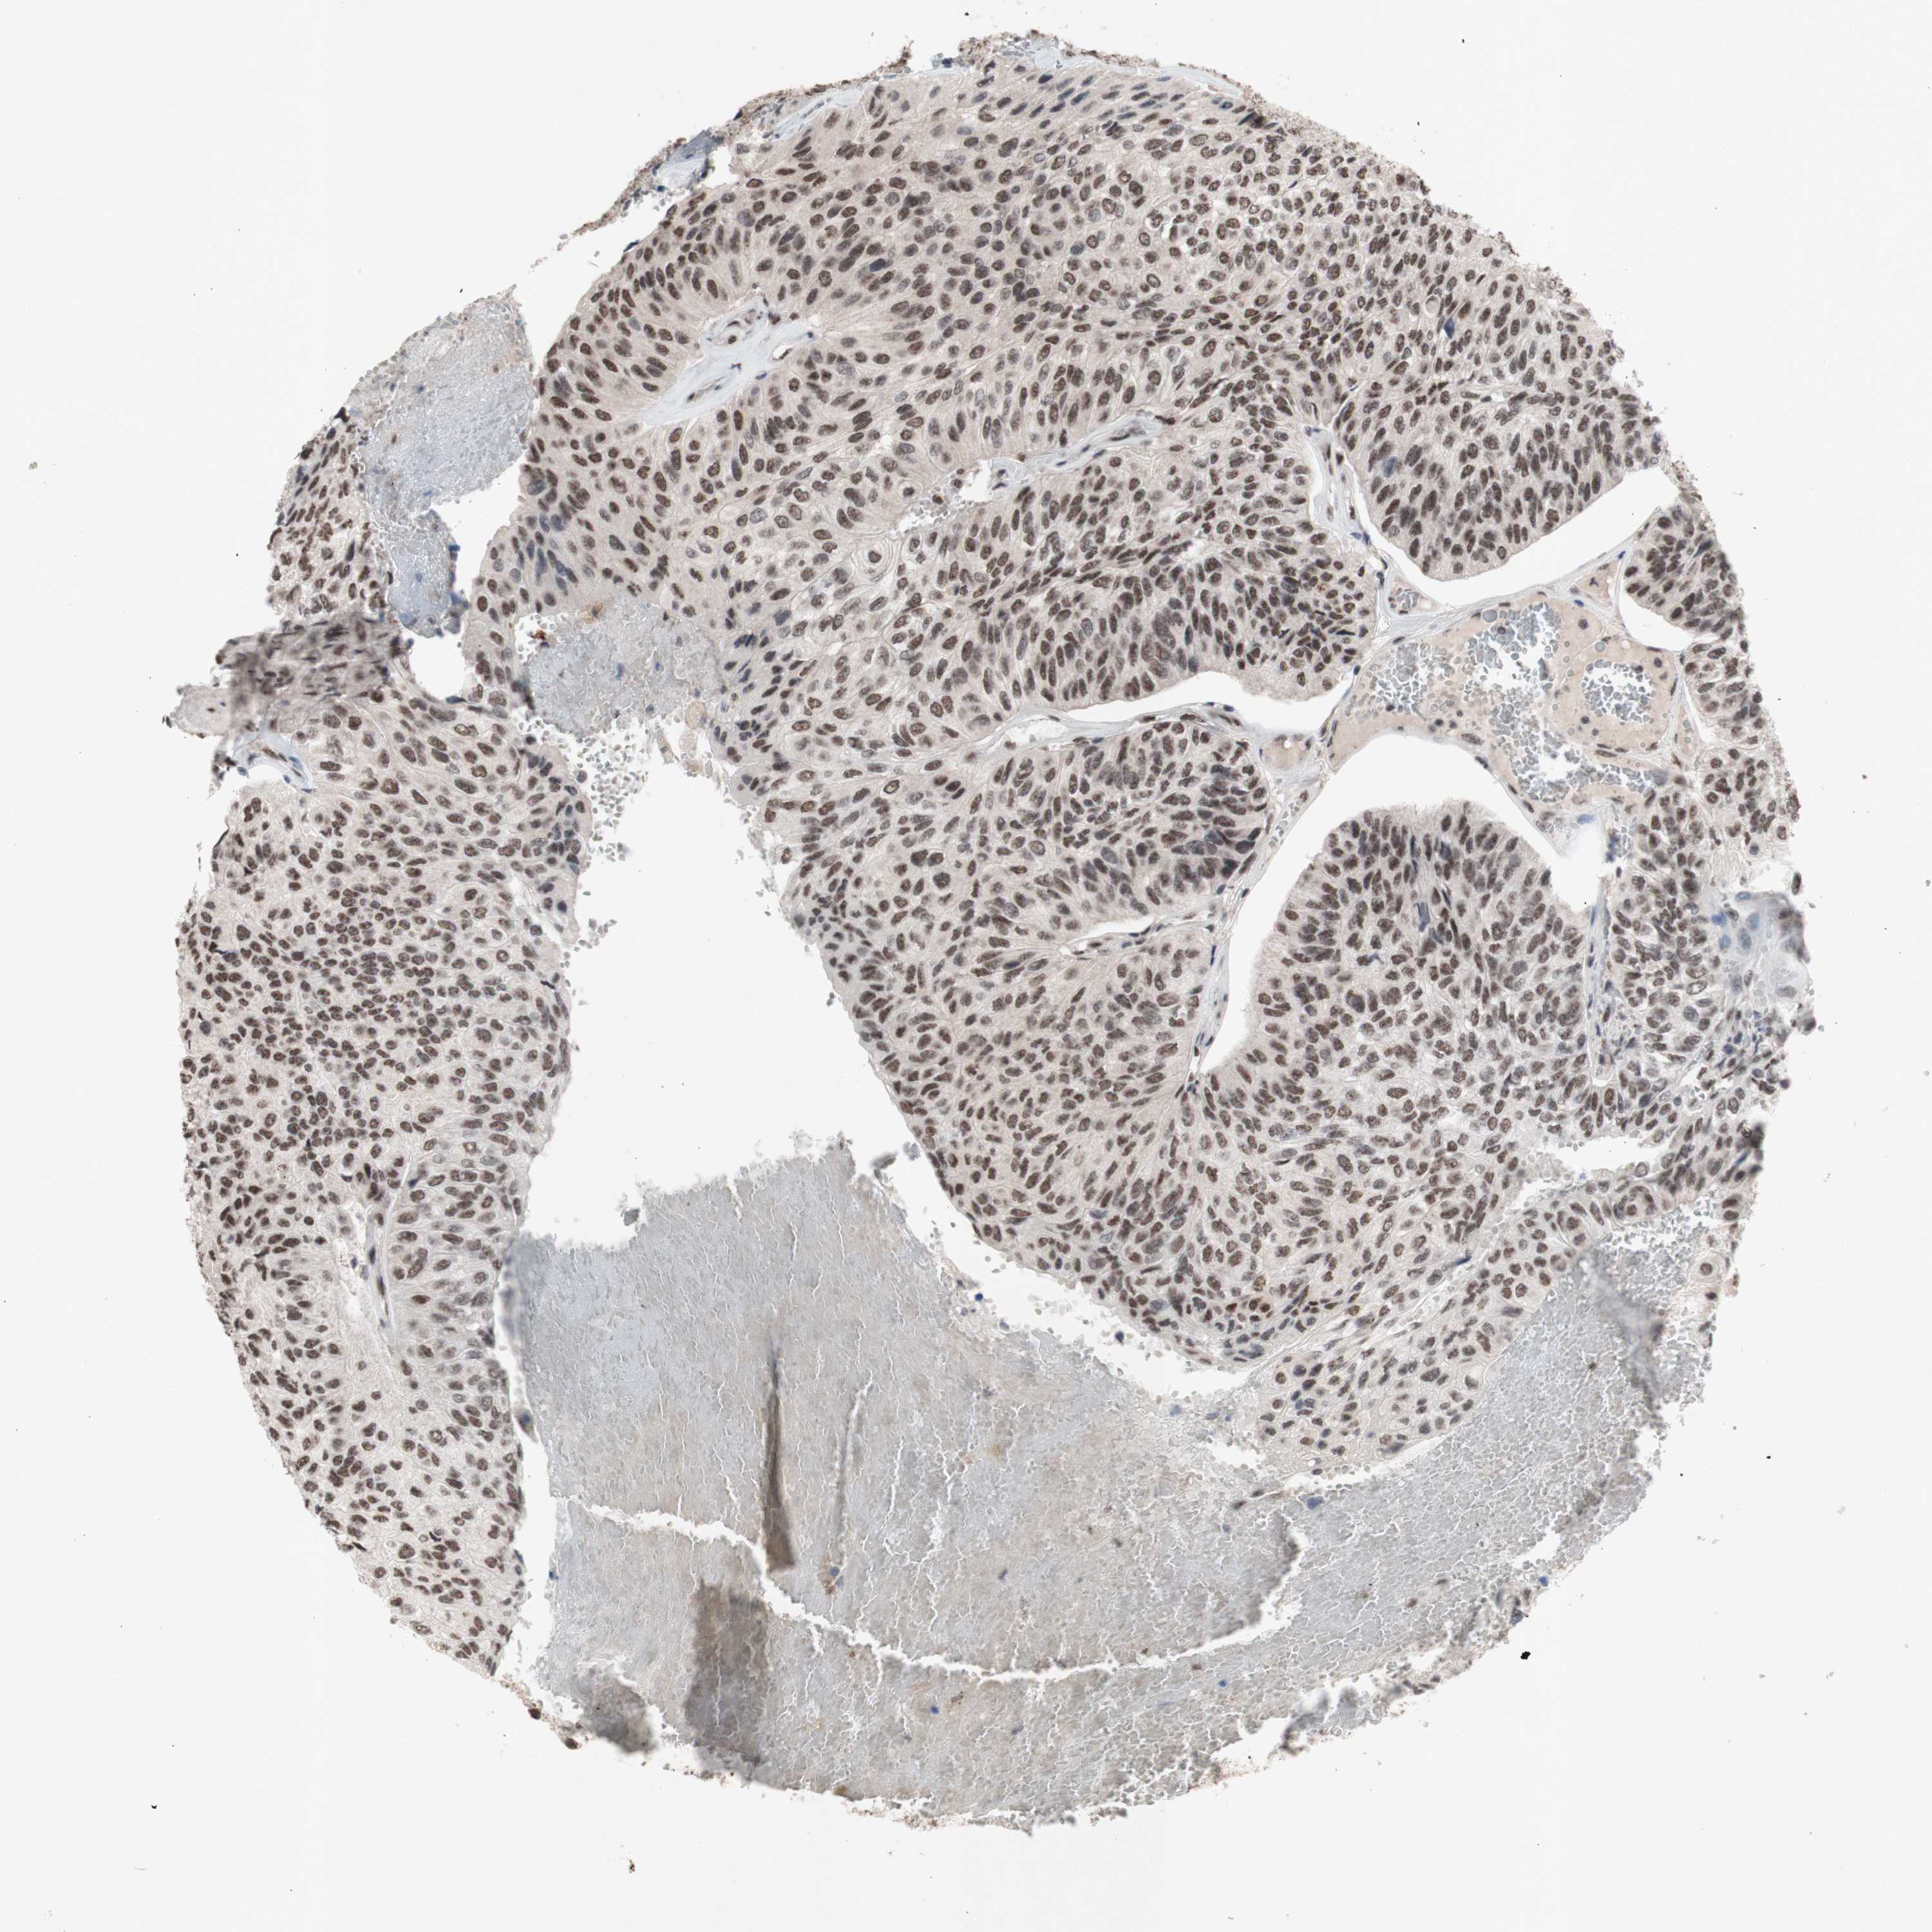

UROTHELIAL CANCER - Protein expressioni

A mouse-over function shows sample information and annotation data. Click on an image to view it in a full screen mode. Samples can be filtered based on level of antibody staining by selecting one or several of the following categories: high, medium, low and not detected. The assay and annotation is described here.

Note that samples used for immunohistochemistry by the Human Protein Atlas do not correspond to samples in the TCGA dataset.

Antibody stainingi

Antibody staining in the annotated cell types in the current human tissue is reported as not detected, low, medium, or high, based on conventional immunohistochemistry profiling in selected tissues. This score is based on the combination of the staining intensity and fraction of stained cells.

Each image is clickable and will lead to virtual microscopy that enables deeper exploration of all samples and also displays staining intensity scores, fraction scores and subcellular localization as well as patient and tissue information for each sample.

Antibody HPA047513

Antibody HPA054689

Antibody CAB009886

Staining

High

Medium

Low

Not detected

Intensity

Strong

Moderate

Weak

Negative

Quantity

>75%

75%-25%

<25%

None

Location

Nuclear

Cytoplasmic/membranous

Cytoplasmic/membranous,nuclear

Urothelial carcinoma, High grade

Urothelial carcinoma, Low grade